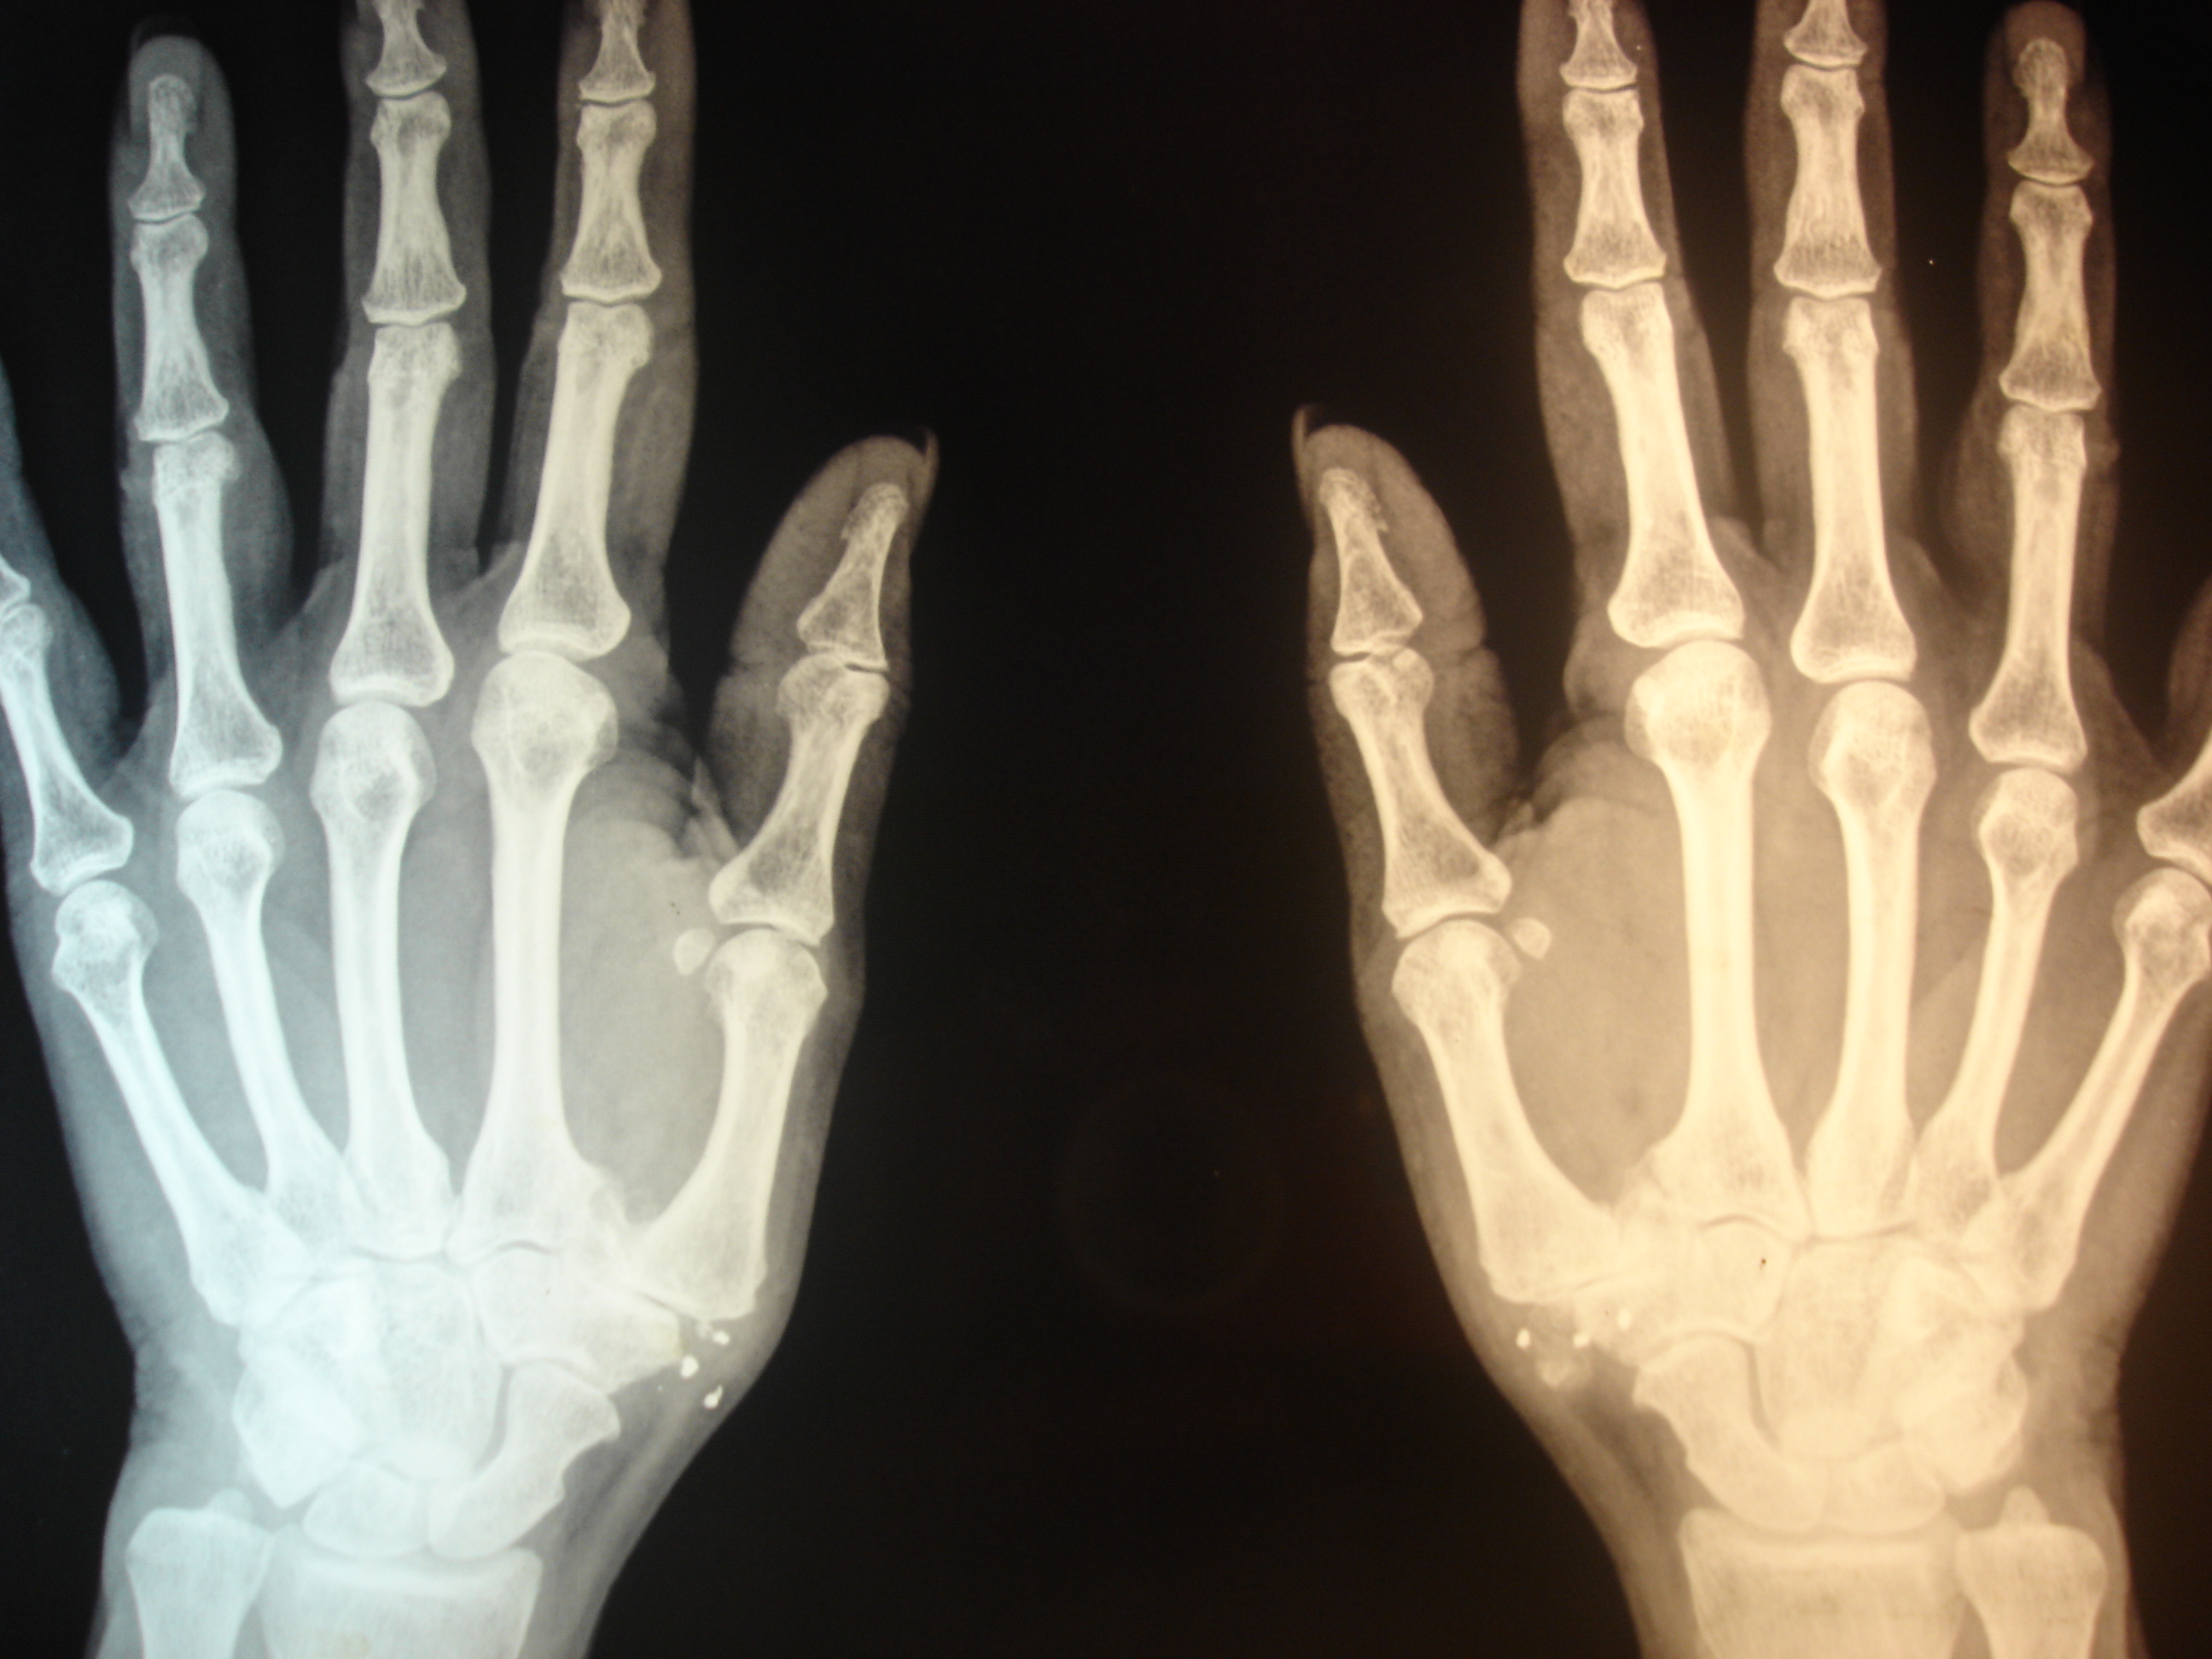

era muy satisfactorio para la paciente (aunque en la mano derecha era muy bueno pero persistía algo de dolor). Luego de 4 meses, en el momento de colocar implantes en las rodillas se colocó un implante más en la cara palmar de la articulación metacarpofalángica que era algo sintomática. Se puede ver en la RX interaoperatoria. El resultado inmediato ha sido muy satisfactorio.

aparente disminución de la calcificación en la mano izquierda

imagen intraoperatoria en la que se puede ver la aguja de implantación